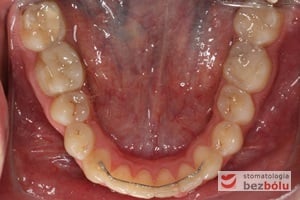

Pacjentka lat 22 zgłosiła się do naszej placówki celem podjęcia leczenia ortodontycznego. Głównym oczekiwaniem pacjentki była poprawa estetyki uśmiechu oraz brak ekstrakcji zębów na drodze do jej uzyskania. Ze względu na liczne stłoczenia zębów w górnym i dolnym łuku, dość duży materiał zębowy w porównaniu z bazą kostną, a także zgryz przewieszony boczny prawostronny po dokładnej analizie cefalometrycznej oraz analizie modeli diagnostycznych zastosowano leczenie bezekstrakcyjne z wykorzystaniem strippingu jako alternatywy dla usuwania zębów, mającego na celu uzyskanie miejsca w łuku na uszeregowanie zębów. Po fazie aktywnego leczenia trwającego 18 miesięcy zastosowano leczenie retencyjne w postaci szyny retencyjnej w łuku górnym oraz retainera stałego w łuku zębowym dolnym klejonego od kła do kła.